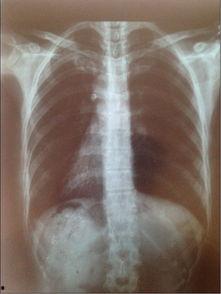

首先,你得知道,胸片是一种医学影像检查,主要用于检查胸部器官,如心脏、肺部等。而2023年的胸片爆料,可是透露了不少关于我们身体健康的新信息。

据《健康时报》报道,2023年的胸片技术有了很大的突破。首先,分辨率更高了,这意味着医生可以更清晰地看到胸部器官的细节。这样一来,对于早期发现肺部疾病,如肺癌等,就有了更大的帮助。